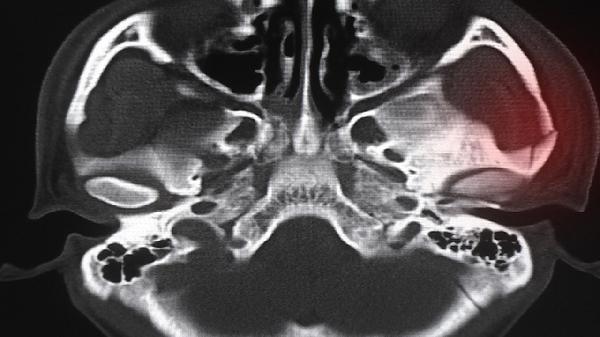

骨骨骺线基本闭合后长高10厘米的可能性较低,但尚未完全闭合时仍存在一定生长空间。骨骨骺线闭合程度需通过X光片确认,完全闭合后骨骼纵向生长停止,部分闭合时可能通过科学干预获得有限身高增长。

骨骺线处于半闭合状态时,长高潜力与剩余生长空间直接相关。此时保证每日摄入足够优质蛋白和钙质,如牛奶、鸡蛋、鱼类等食物,有助于骨骼矿化。规律进行跳跃类运动如篮球、跳绳,可刺激生长板软骨细胞增殖。夜间深度睡眠期间生长激素分泌量占全天的70%,保持22点前入睡能优化激素分泌。部分青少年在骨骺闭合前1-2年可能出现生长加速期,这个阶段加强营养和运动可能获得3-5厘米自然增长。

骨骺完全闭合后长高主要依赖脊柱椎间盘压缩恢复和姿势矫正。通过悬垂运动拉伸脊柱,可改善因日常重力压迫导致的椎间隙变窄,获得1-3厘米视觉增高。专业形体训练能纠正驼背、骨盆前倾等不良体态,使身高测量值增加1-2厘米。鞋垫增高、发型修饰等外在方式能临时增加2-5厘米视觉高度。极少数病理性矮小患者在骨骺闭合后仍需生长激素治疗,但需严格评估骨龄和激素水平。